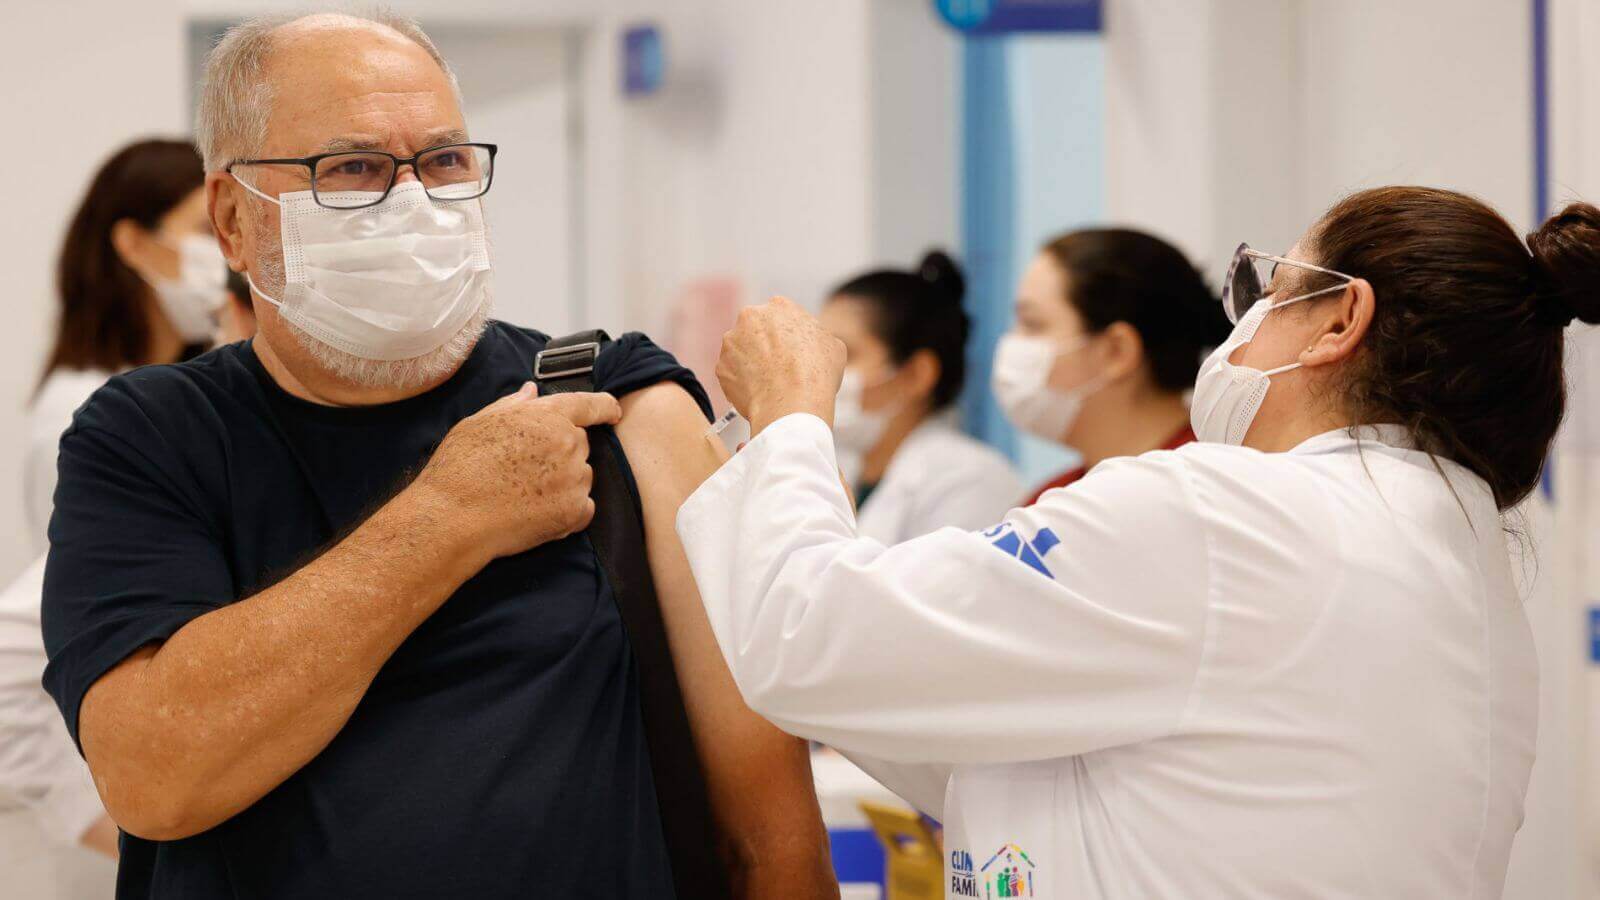

Governo libera vacina bivalente contra a Covid-19 para todos acima de 18 anos

Vacinação com a bivalente é ampliada após atingir apenas 16% do público-alvo nas primeiras etapas da campanha.

Na noite desta segunda-feira (24), o Ministério da Saúde anunciou a liberação da vacina bivalente de reforço contra Covid-19 para qualquer pessoa acima de 18 anos de idade. Podem receber a bivalente quem já recebeu, pelo menos, duas doses de vacinas monovalentes, como Coronavac, Astrazeneca ou Pfizer. A aplicação da bivalente deve acontecer em um intervalo de pelo menos quatro…

Covid: Jundiaí abre agendamento para vacina bivalente para idosos e imunossuprimidos

O imunizante é uma versão atualizada dos já existentes contra a Covid-19 e pode oferecer uma proteção ainda maior contra a cepa original e subvariantes.

A Saúde de Jundiaí abrirá novo agendamento para doses de vacina Pfizer bivalente contra a Covid-19, nesta terça-feira (28), às 15h. Idosos com 70 anos ou mais e imunossuprimidos com 12 anos ou mais podem agendar pelo site ou APP Jundiaí. Para tomar a dose bivalente, a pessoa deve ter recebido, no mínimo, duas doses da vacina monovalente (Janssen, Pfizer, CoronaVac ou Astrazeneca).…